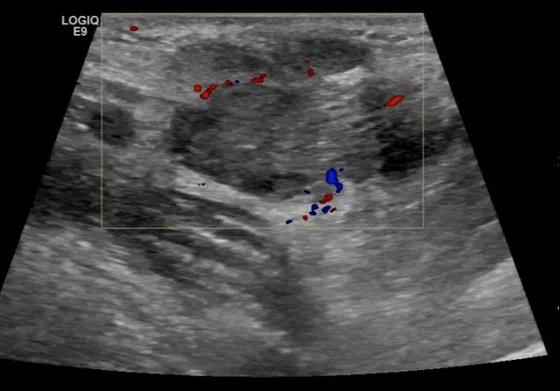

第二例是食管癌患者,术后半年余锁骨上固定淋巴结可触及肿大,疼痛非常明显,系统治疗后无缓解,患者希望通过局部处理缓解症状。造影显示强化信号明显,结节部分区域坏死,故主要针对强化区域从后向前的逐层的消融,皮下进行液体隔离减少烫伤。热消融后影像显示血流增强消失,弹性、硬度增高,一个月后复查显示充盈缺损,完全消融,疗效远超预期。

(病例2图例)